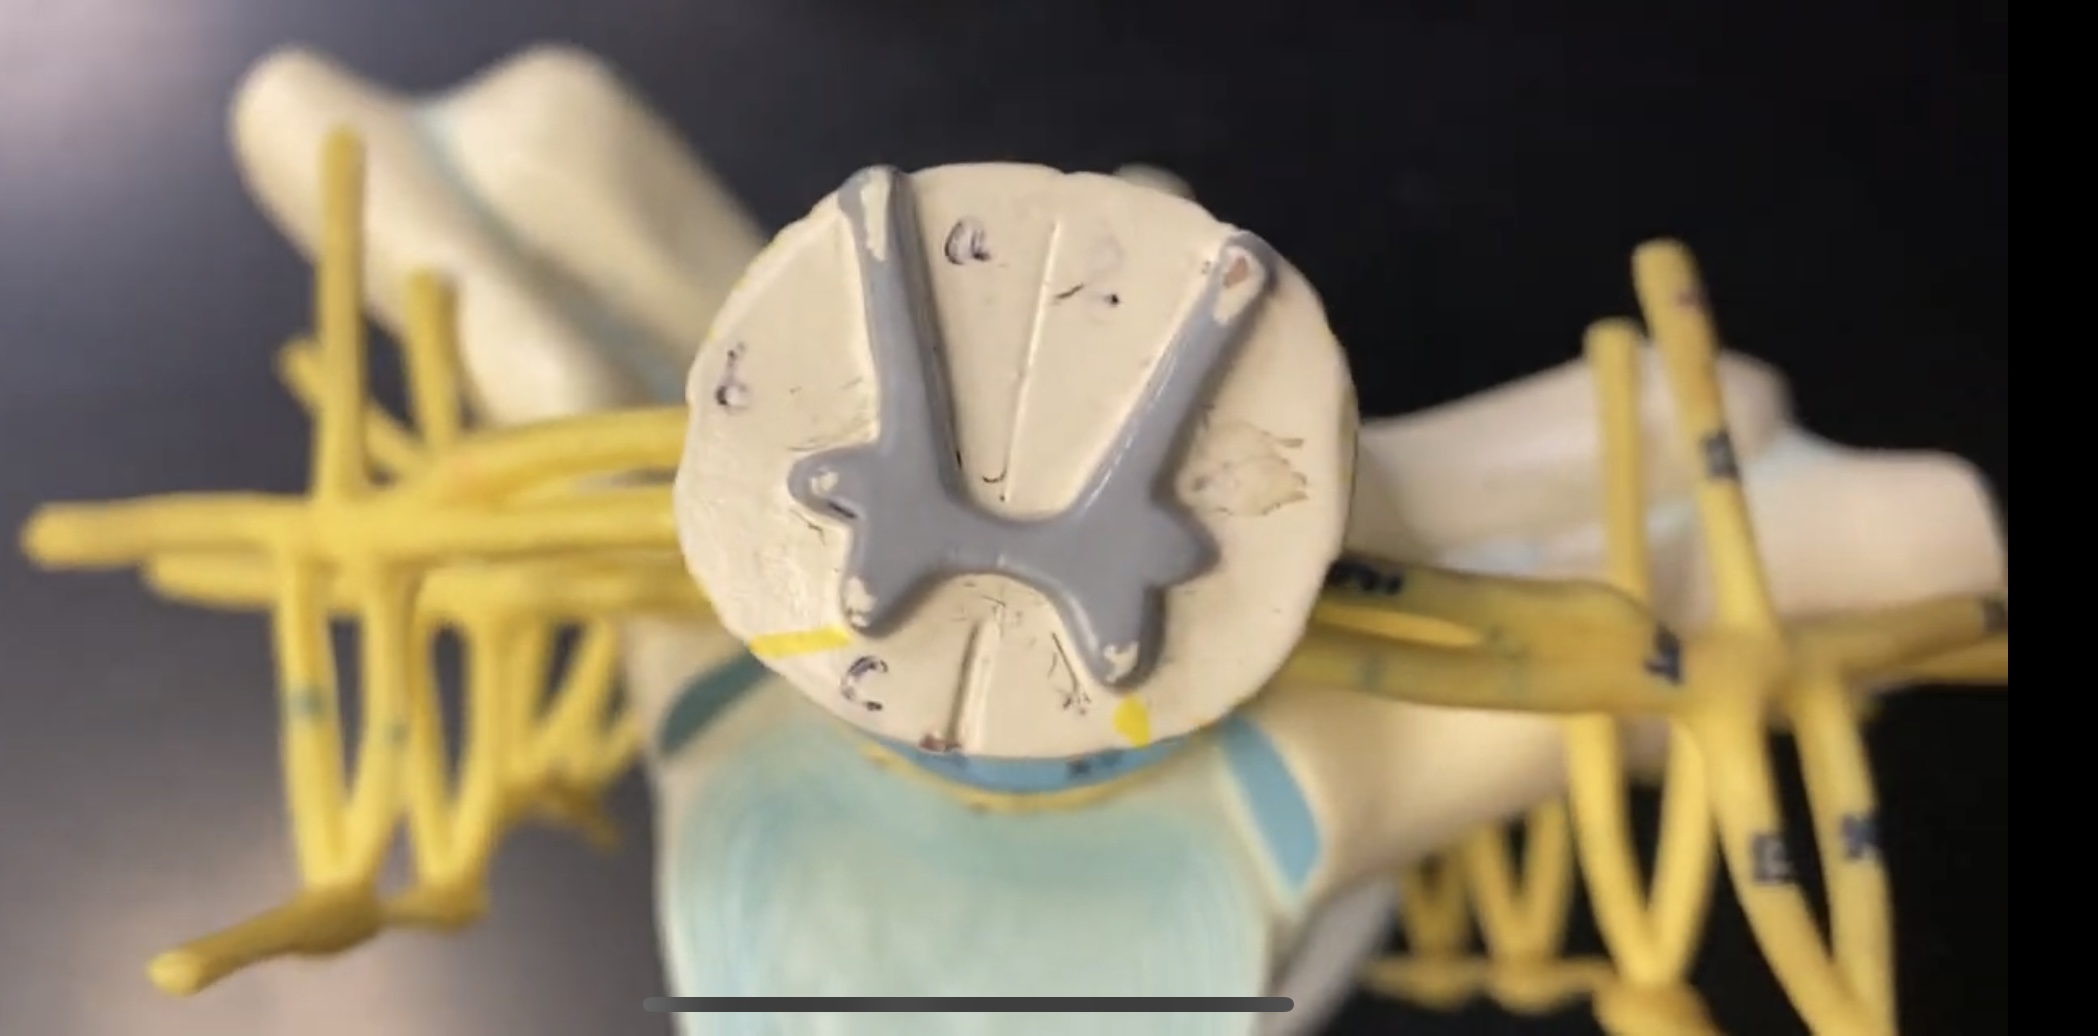

What is the groove here?

anterior median fissure

posterior median sulcus

posterior (dorsal) horn

posterior (dorsal) horn; R—>L

anterior (ventral) horn

lateral horn (selected models)

gray commissure

central canal

anterior column

lateral column

posterior column

white commissure